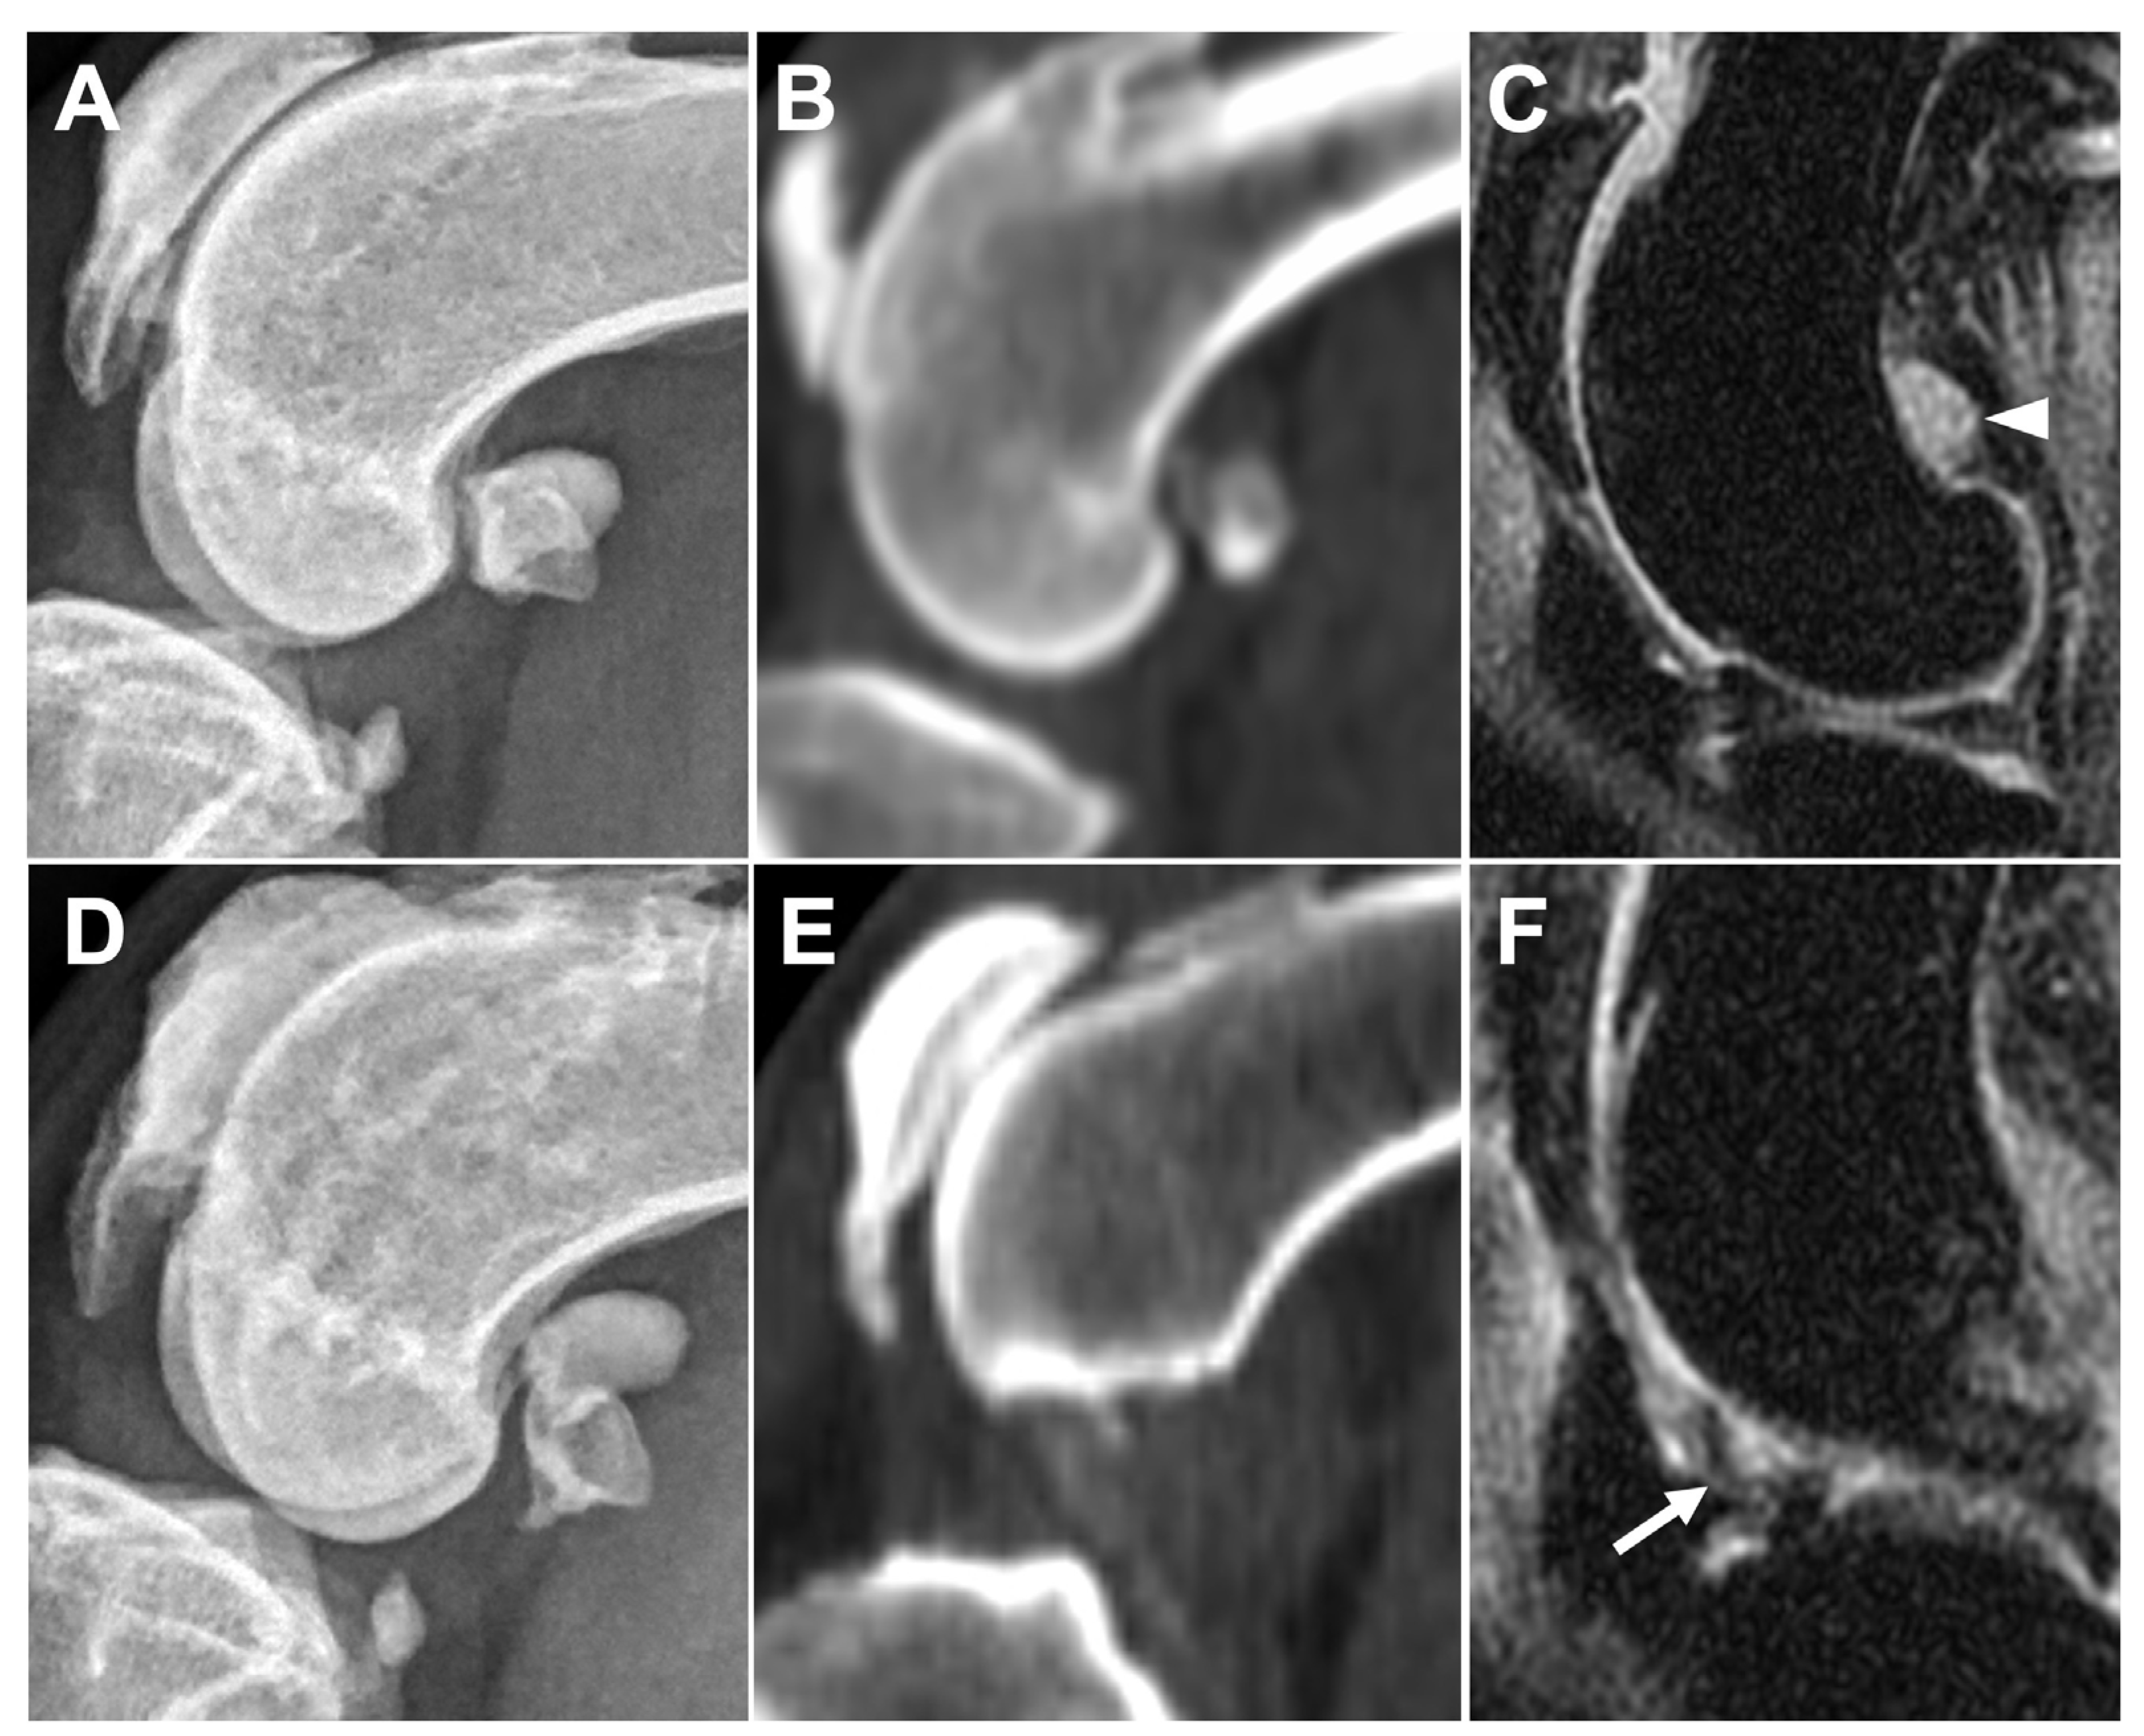

3.2.4. Subchondral Bone Lesions

3.2.5. Meniscal and Cartilage Lesions